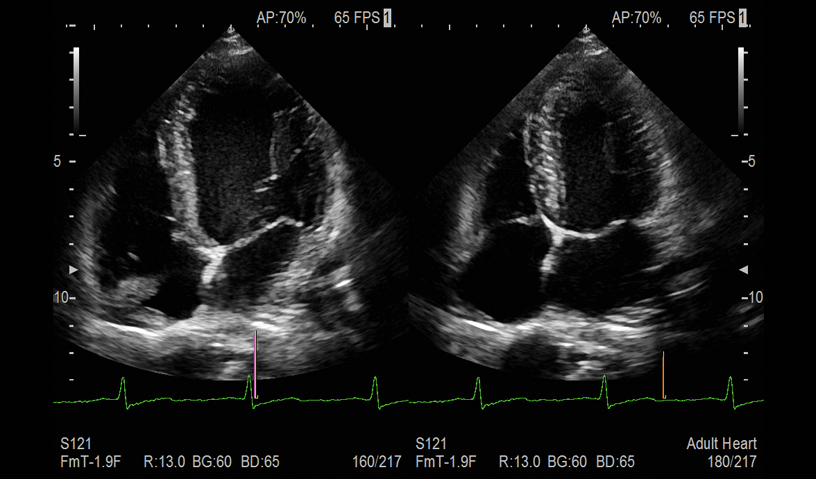

- Beat Mode:automated detection of End Diastolic & End Systolic frames

LA Volume